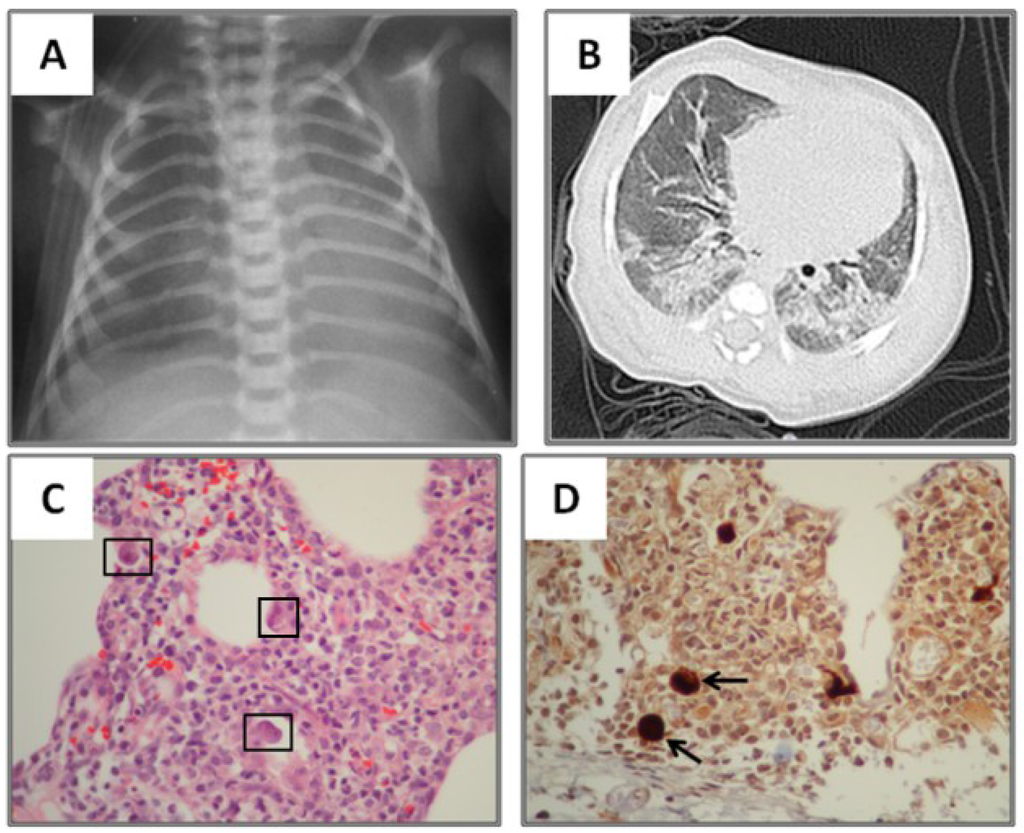

| Radiological variables | |

| Abnormal lung images, n (%) | 15 (100) |

| Ground-glass opacity, n (%) | 12 (80) |

| Consolidation, n (%) | 12 (80) |

| Atelectasis, n (%) | 6 (40) |

| Air trapping, n (%) | 5 (33) |

| Nodular pattern, n (%) | 3 (20) |

| Reticular pattern, n (%) | 1 (6) |

| Tree-in-bud pattern, n (%) | 1 (6) |

3.2. Radiological Findings in CMV Lung Infection

| Lung biopsy, n (%) | 5 (33) |

| Biopsy confirmed CMV, n (%) | 5/5 (100) |